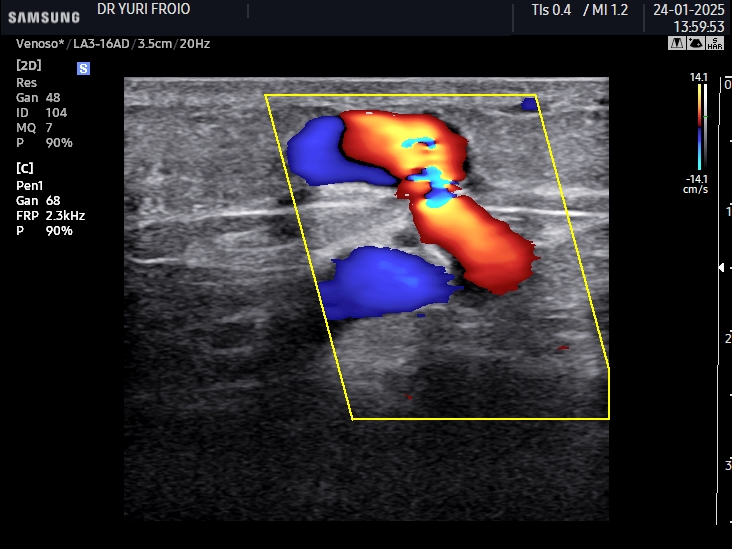

Ecografia Vascular com Doppler

A ecografia vascular com Doppler avalia o fluxo sanguíneo em artérias e veias identificando obstruções, varizes e tromboses. É um exame não invasivo, essencial para diagnóstico e acompanhamento de doenças vasculares. Proporciona informações detalhadas para uma abordagem clínica precisa.